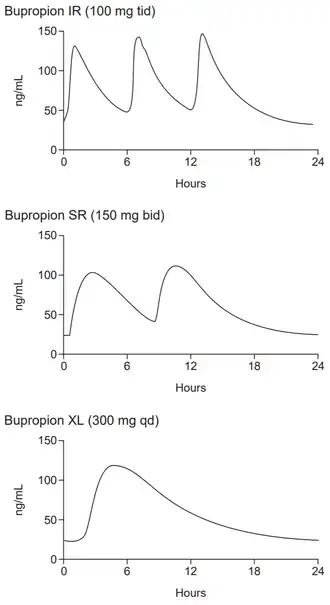

After oral administration, bupropion is rapidly and completely absorbed, reaching the peak blood plasma concentration after 1.5 hours (tmax). Sustained-release (SR) and extended-release (XL) formulations have been designed to slow down absorption, resulting in tmax of 3 hours and 5 hours, respectively.[108] Absolute bioavailability of bupropion is unknown but is presumed to be low, at 5–20%, due to the first-pass metabolism. As for the relative bioavailability of the formulations, the XL formulation has lower bioavailability (68%) compared to the SR formulation and immediate release bupropion.[2]

In 1996, the US Food and Drug Administration (FDA) approved a sustained-release formulation of alcohol-resistant bupropion called Wellbutrin SR, a tablet intended to be taken twice a day (as compared with three times a day for immediate-release Wellbutrin).[183] In 2003, the FDA approved another sustained-release formulation called Wellbutrin XL, a hard-shelled tablet intended for once-daily dosing.[184] Wellbutrin SR and XL are available in generic form in the United States and Canada. In 1997, bupropion was approved by the FDA for use as a smoking cessation aid under the name Zyban.[185][183] In 2006, Wellbutrin XL was similarly approved as a treatment for seasonal affective disorder.[186][187]